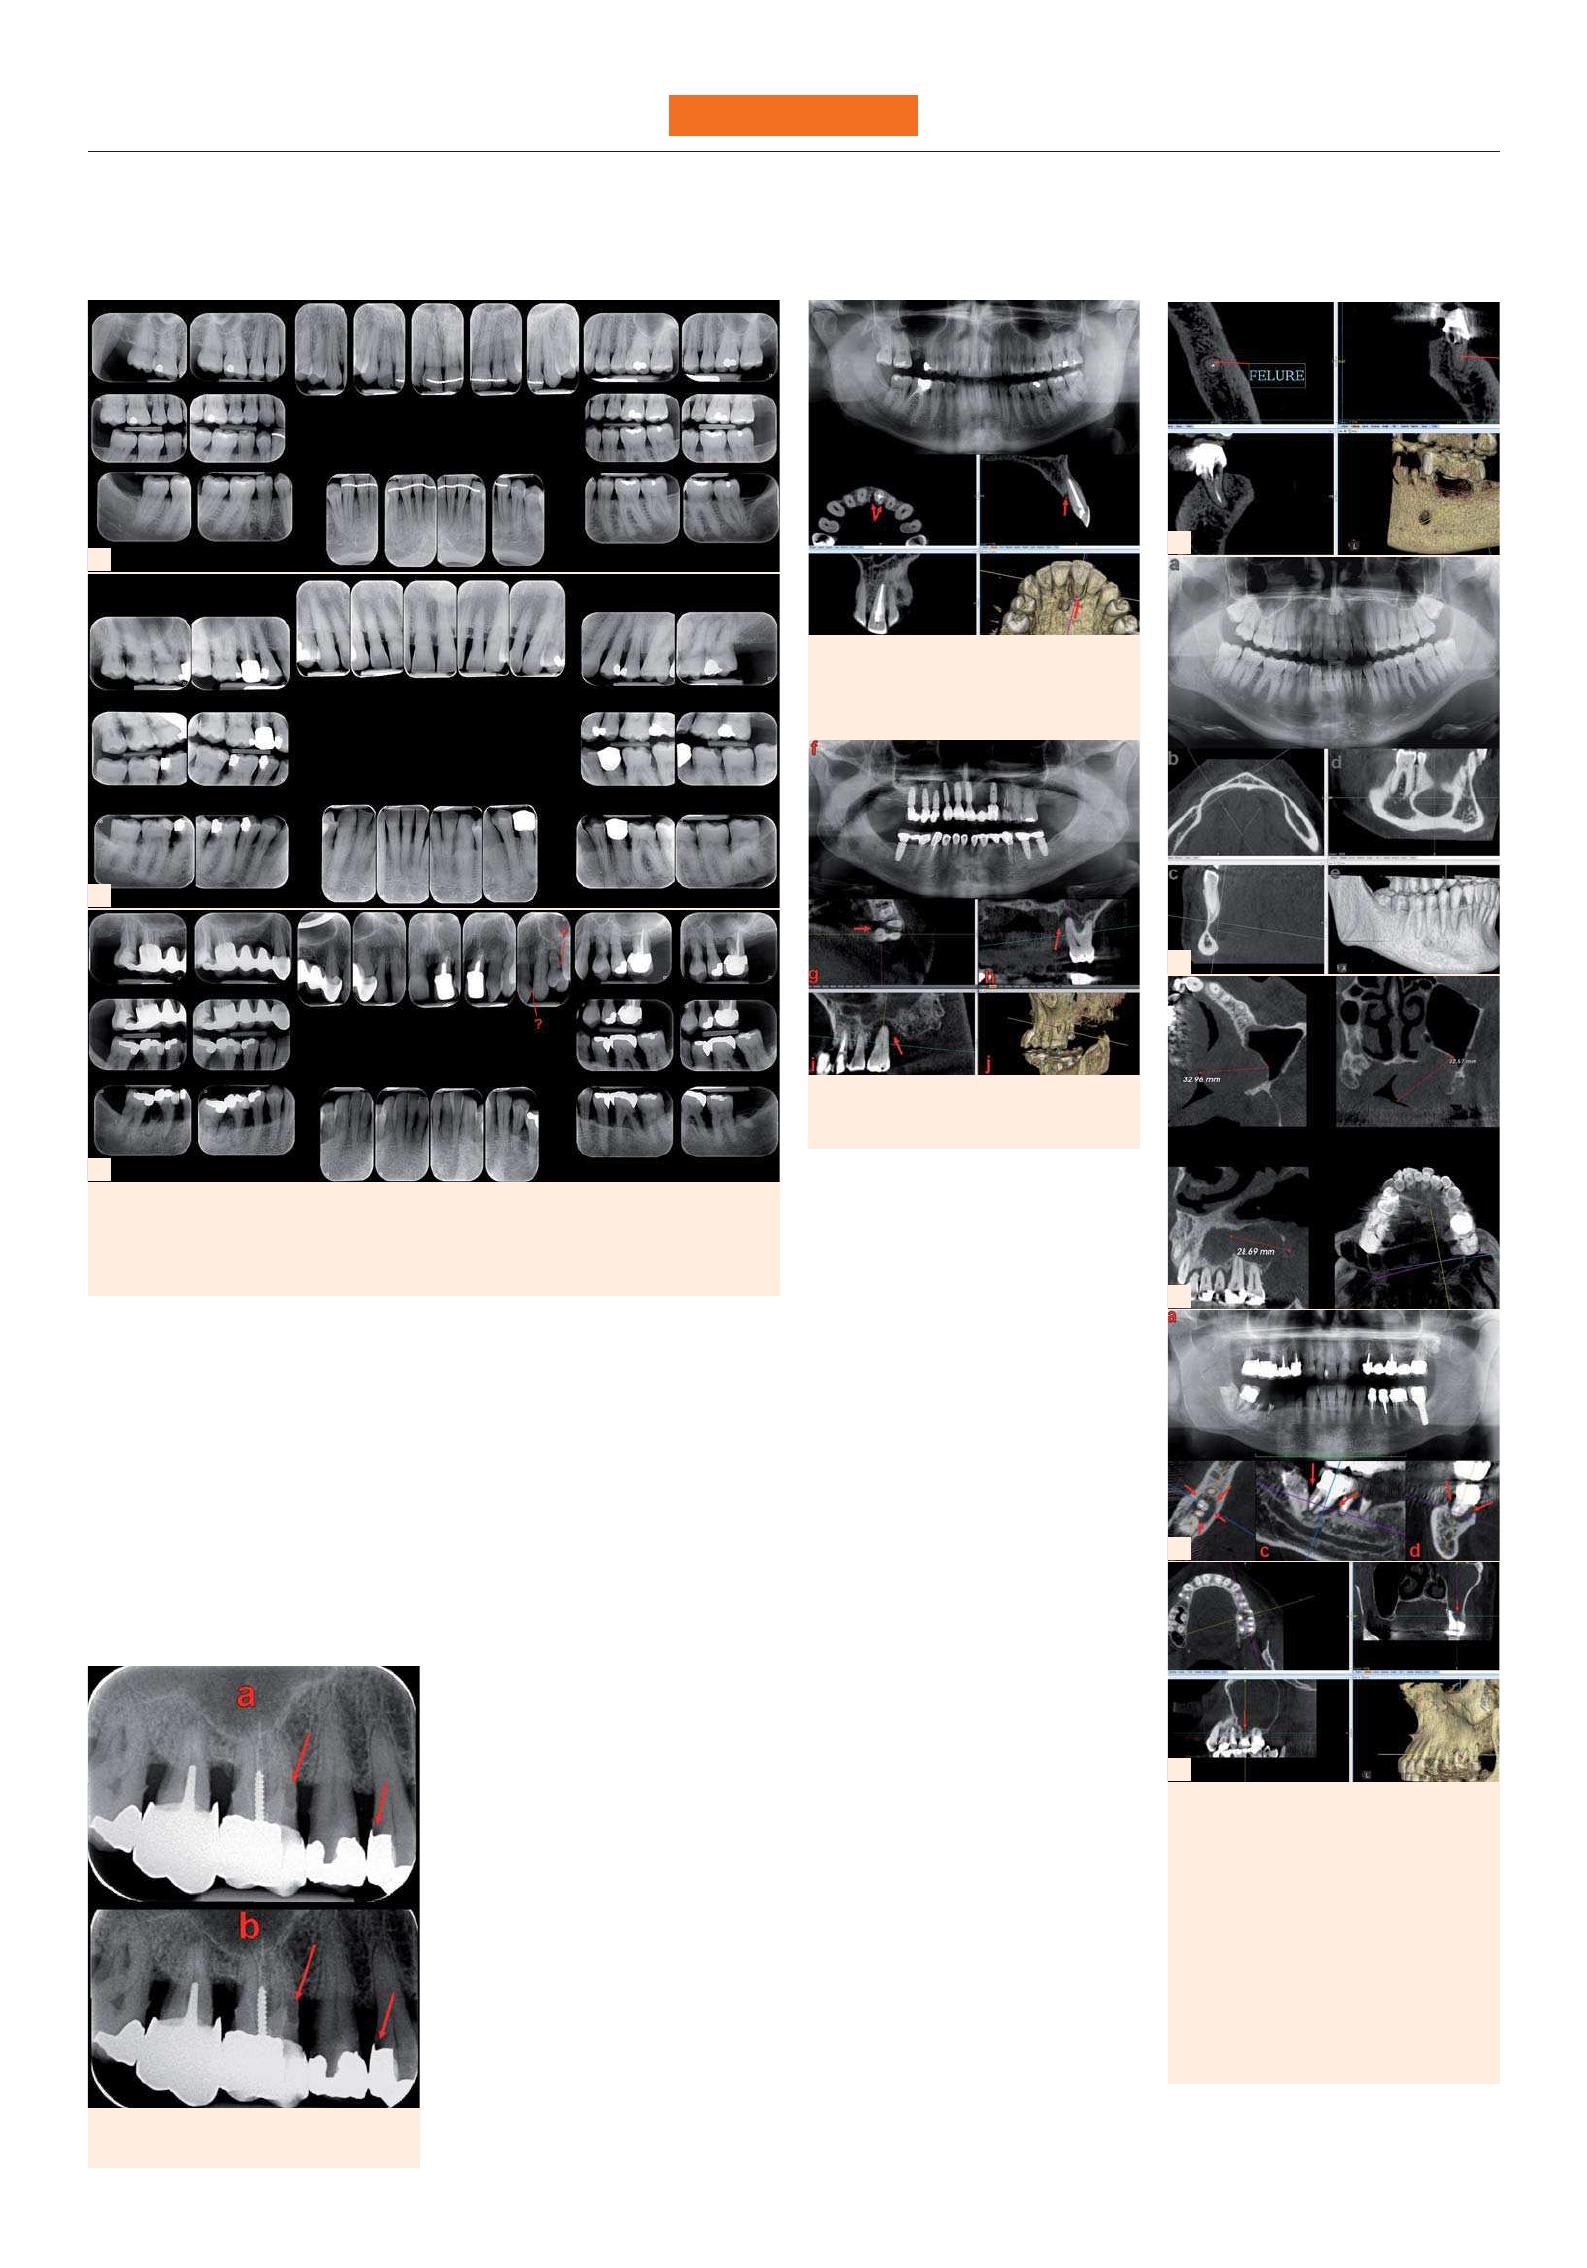

a. Clichés rétro-alvéolaires long cone (RA):

– Un cliché de référence est pratiqué le

jour de la pose de la prothèse: normale-

ment,  le niveau de la crête doit se situer

à la jonction pilier-implant. (Figs. 21 et 22)

– Ce cliché devra aussi détecter un excès

de ciment (Fig. 24) ou un hiatus par dé-

faut de serrage.

b. Un panoramique dentaire est souvent

suffisant en cas d’implants multiples

(Fig. 22), mais devra être completé par des

RA au moindre doute.

c.  Les examens RA de surveillance ulté-

rieure doivent permettre

– de mesurer la perte osseuse:

· normalement , elle est au maximum

de 1,2 mm la première année et de

0,1 mm par an les années suivantes ;

· en cas de péri-implantite (Figs. 23 à 25),

apparition d’un cratère plus ou moins

profond, centré par l’implant ;

– de préciser le nombre de spires expo-

sées (Figs. 24 et 25) ;

– d’éliminer les complications bioméca-

niques:

· désostéointégration, évoquée par un

liseré clair à l’interface os-implant,

· absence d’ostéointégration et péri-im-

plantite apicale,

· fracture du col implantaire, dont

l’aspect de cratère en demi-lune est

proche de celui d’une  péri-implantite :

· en cas d’implant unitaire, la mobilité

de la couronne permet le diagnostic;

· en cas d’implants multiples, la dépose

du bridge peut être nécessaire au dia-

gnostic, si le cone beam est impossi-

ble ou insuffisant.

d. Le cone beam permet au moindre

doute:

– d’évaluer la perte osseuse en trois di-

mensions, précisant

· le nombre de murs résiduels,

· ainsi que la morphologie du défaut, le

nombre réel de spires exposées si un

doute subsiste après les RA

· et ses rapports avec les piliers adja-

cents, les corticales (Figs. 29b, 31 et 32) et

les obstacles anatomiques ;